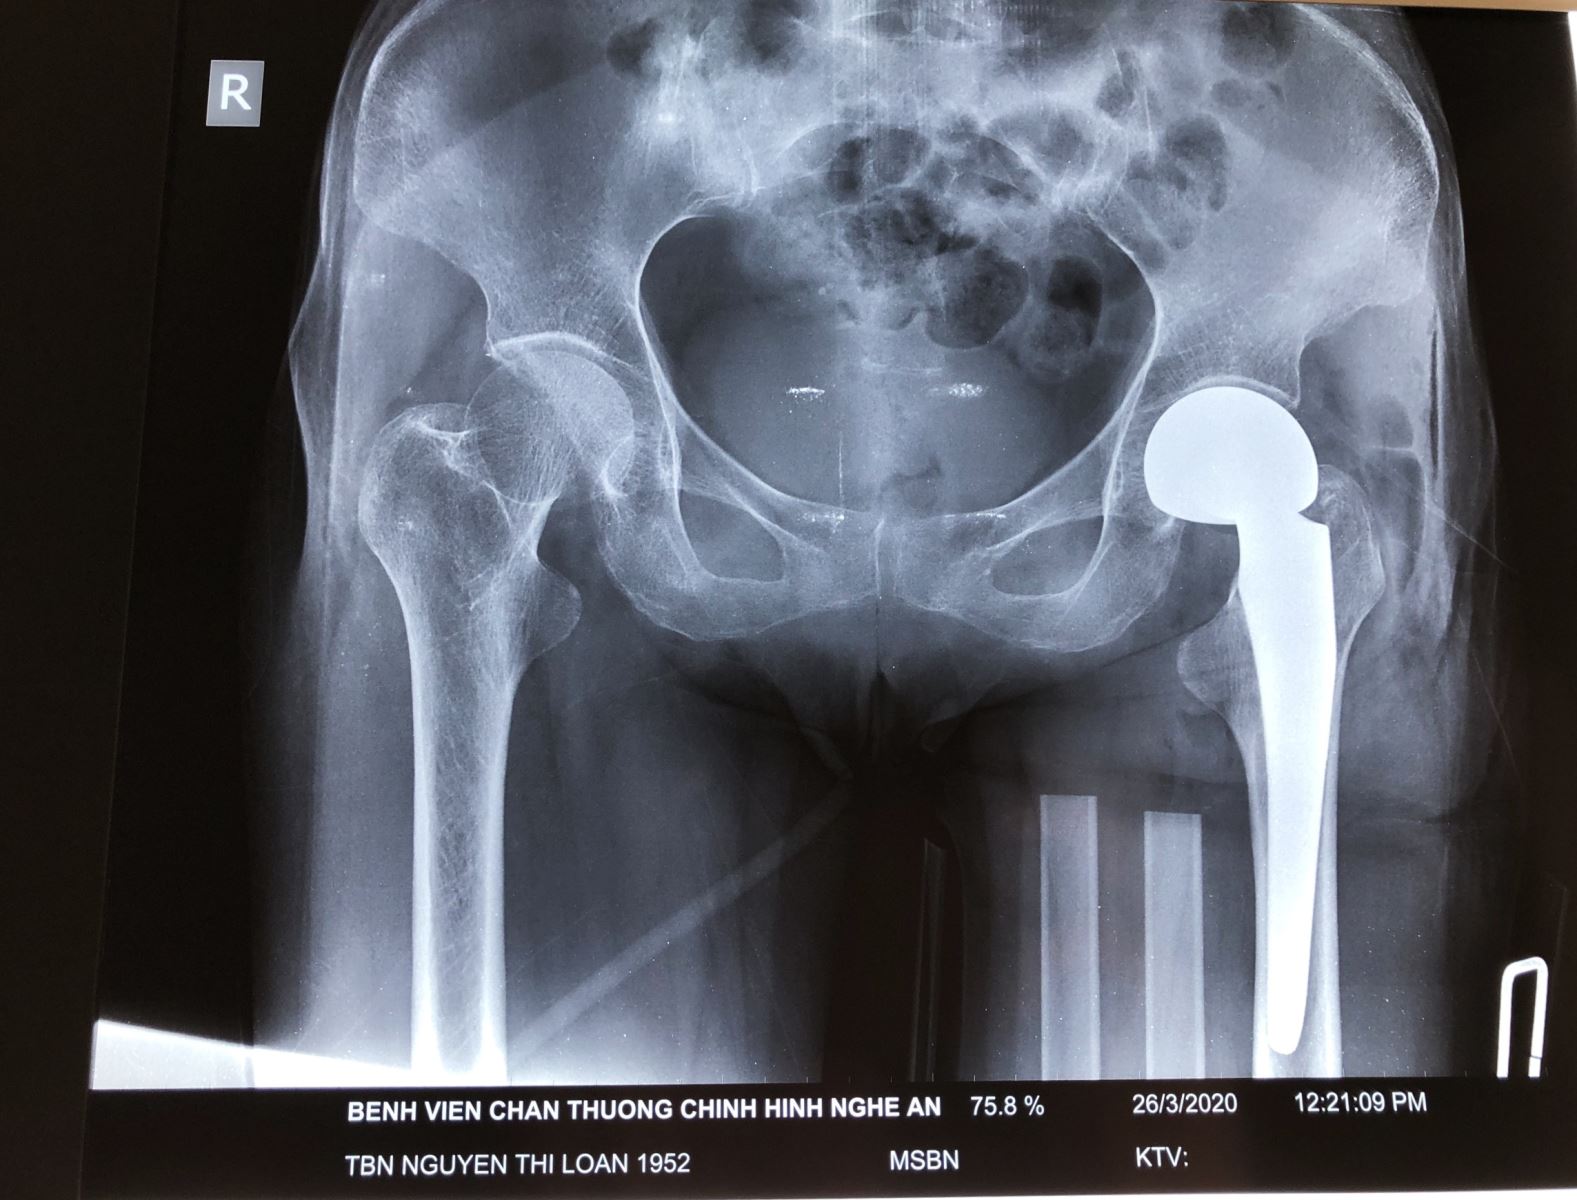

Hình ảnh phim chụp Xquang của bệnh nhân trước và sau phẫu thuật thay khớp háng